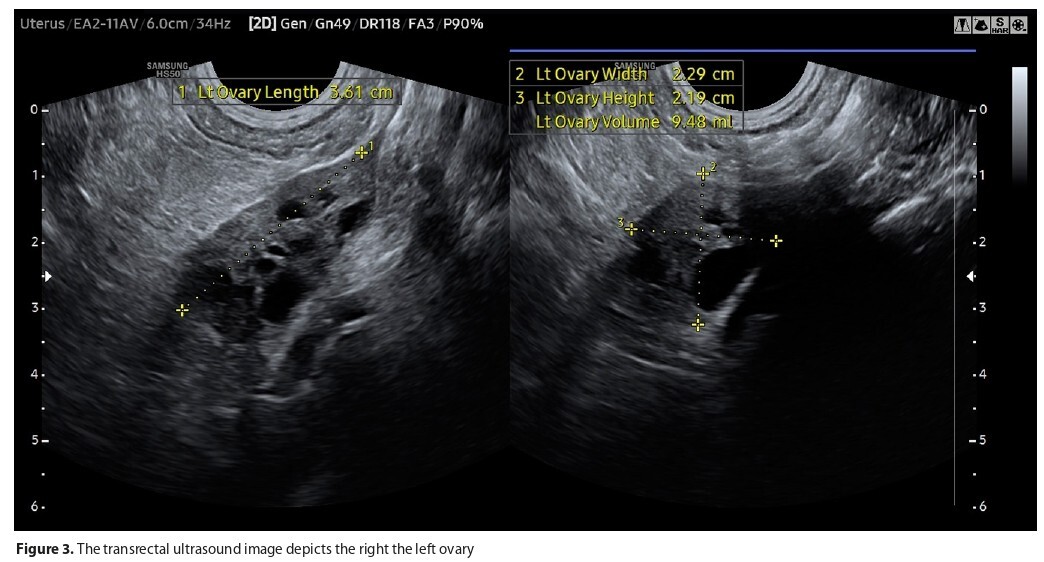

Mayer-Rokitansky-Küster-Hauser (MRKH) syndrome is characterized by uterus and vagina aplasia with normal ovary function. The first symptom is primary amenorrhea. It is necessary to exclude potential causes, among which MRKH syndrome takes second place. A 15-year-old patient was first admitted to the gynaecology clinic due to the primary amenorrhea and abdominal pain. The girl had received ALL chemotherapy at the ages of seven and eight. Hormonal tests showed no ovarian dysfunction. In the transrectal USG performed by a paediatric gynecologist a 2.5cm long vaginal fragment was visualized, MRI confirmed a rudimentary uterus. The girl was offered vaginal correction by dilators. Intercourse attempts were still painful despite the treatment, hence the patient agreed to surgery. The diagnosis of MRKH syndrome in paediatric patients can be complicated by the coexistence of other conditions presenting with primary amenorrhea, especially among patients after chemotherapy.